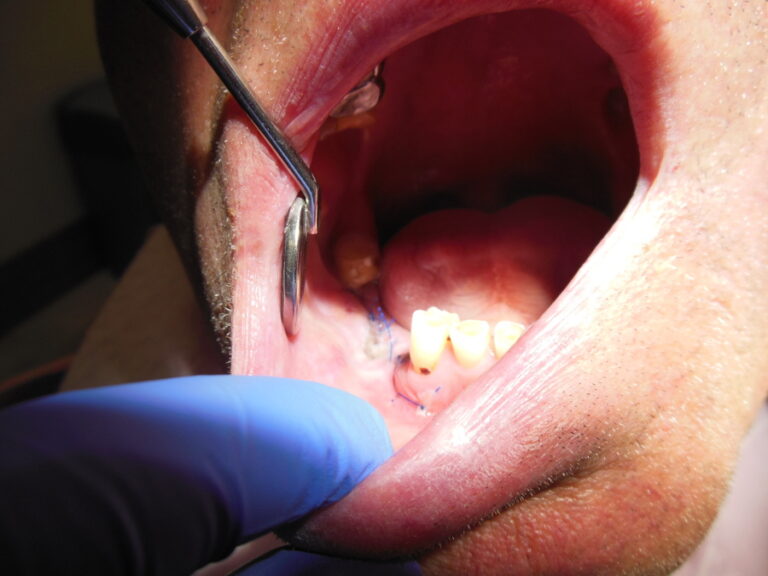

Przykłady zabiegów

Ortodoncja CBCT

Leczenie chirurgiczno-ortodontyczne wad zębowych z zastosowaniem tomografii spiralnej CBCT w naszej klinice.